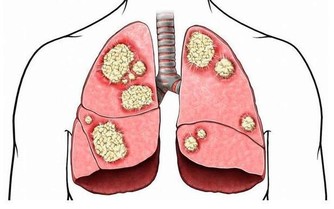

如果人體缺乏維生素C,就會對健康帶來嚴重影響,包括敗血症、牙周出血、蛀牙、多汗、軟骨病等。